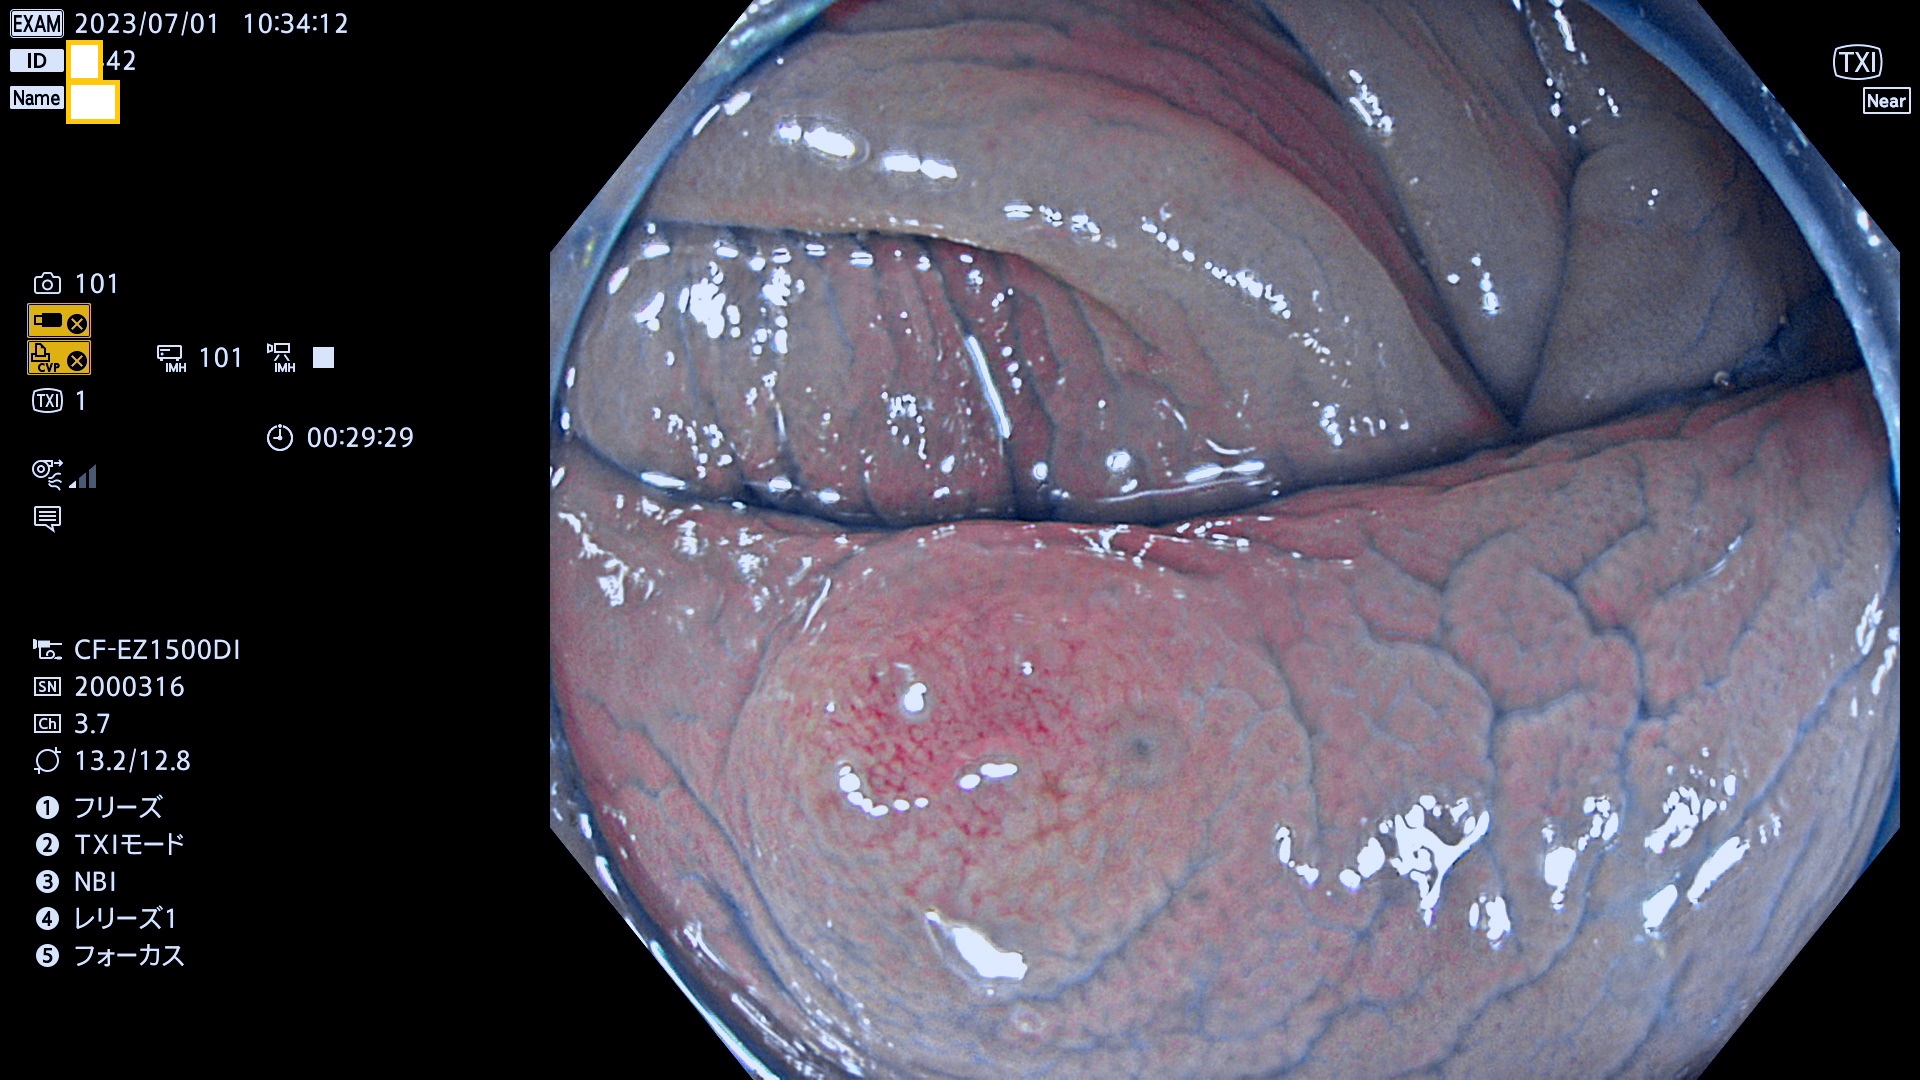

「表面型腫瘍」の中で、完全に平坦な物をUb、陥凹している物をUcと呼びます。平坦隆起型(Ua)よりも、発見が難しく危険な病変です。このタイプの発見率は「腺腫発見率」よりも、遥かに重要な意義があります。

抽出の対象期間 2023年6月29日(木)〜7月2(日)の4日間(48件の検査)8件